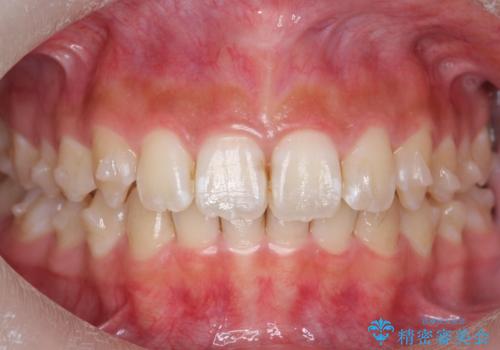

前歯の並び インビザライン 非抜歯で 深いかみ合わせの治療

- 前歯の並びを気にして来院。

上の前歯が内側に倒れこんでいました。

インビザラインで前歯の並びを整えています。

前歯の重なりが大きいいわゆる過蓋咬合を呈していましたが、ある程度適正な重なりにすることができました。